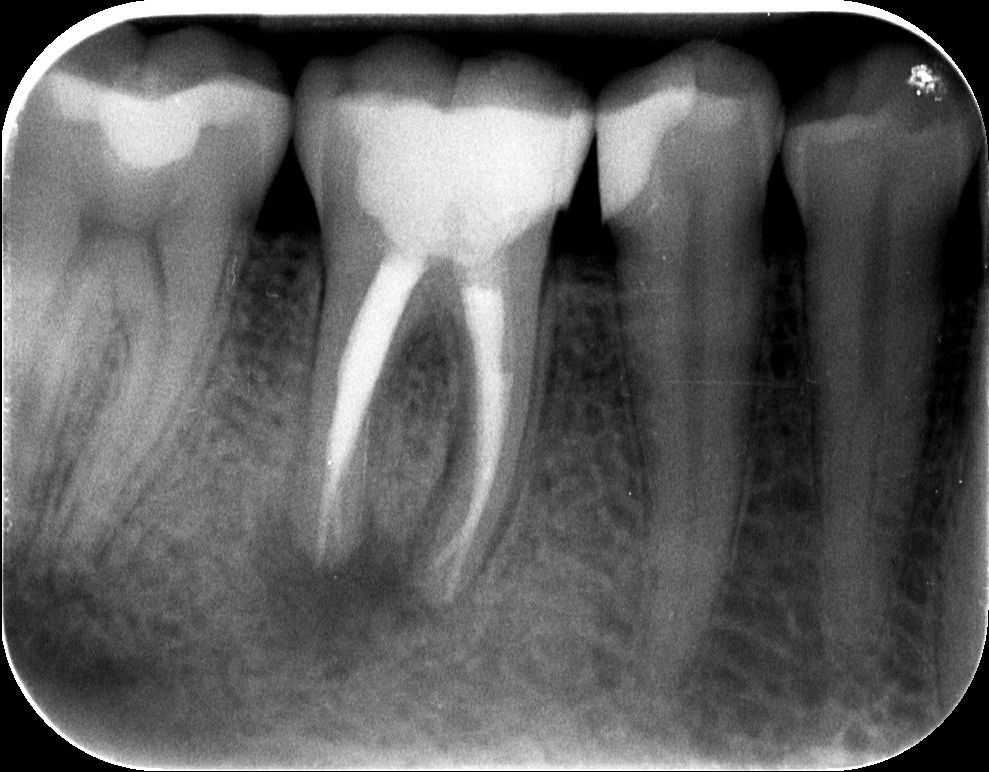

Dr. Kovács Kitti páciense egy három éve készült gyökértöméssel kapcsolatos panaszával kereste fel rendelőnket. A kérdéses fog az utóbbi időben bizonytalan panaszokat produkált. Néha kifejezetten fájt, néha a páciens „érezte”, hogy van foga, néha pedig teljesen panaszmentes volt. A vizsgálatot egy kis röntgenfelvétel készítésével kezdtük, majd ezt tüzetes szájüregi vizsgálat követte. A fog kopogtatásra érzékeny volt, illetve a röntgenfelvételen egyértelműen látható a csontban lévő krónikus gyulladás (amelyet az alsó képen pirossal rajzoltunk körbe), illetve az ezt kiváltó ok, a rövid gyökértömés (amelynek hiányzó szakaszát sárgával jelöltük).

mikroszkópos gyökérkezelés 1.kép